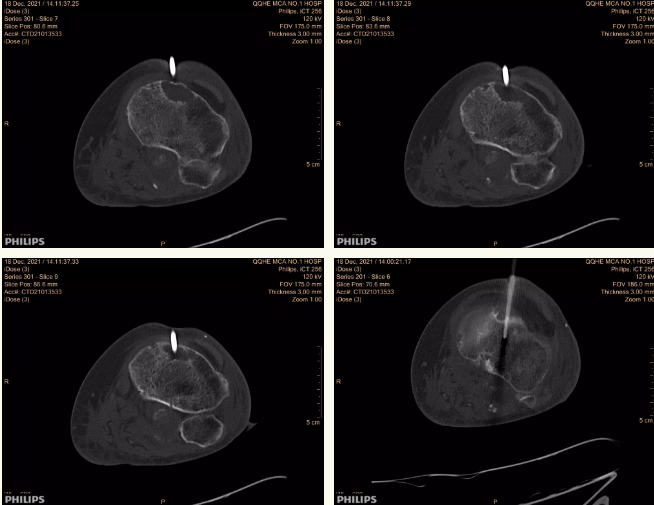

经过充分沟通及征得陈阿姨与家属的同意后,12月18日下午,在影像中心孙生健医生的密切配合下,王雪峰副主任顺利完成了特色微创诊断手术——胫骨病损穿刺活检。术中大体病理证实病人为“胫骨近端骨梗死”,同时将所得标本送检,待进一步明确诊断后,以指导后续治疗。由于穿刺活检的同时对骨破坏区域进行减压,手术后陈阿姨左膝关节疼痛立即得到缓解,一家人非常开心满意。

术中CT引导定位穿刺,精确穿刺病损部位。